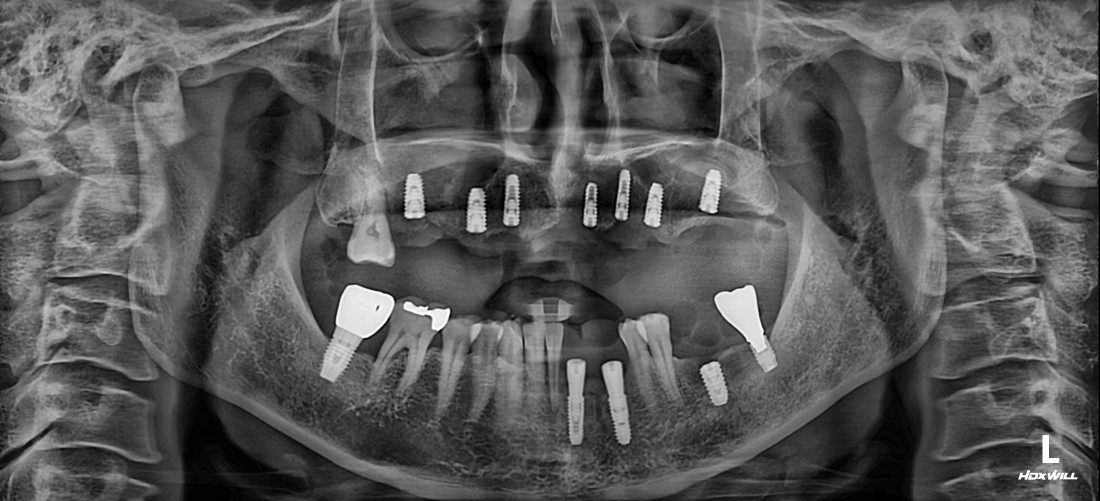

임플란트 수술 후에 통증이 매우 심한 경우는

잇몸절개를 많이 했을 확률이 높습니다.

전남광주 임플란트치과에서는

잇몸절개를 하지 않고 무절개로 하거나,

최소한으로만 절개하는

디지털 가이드 임플란트 수술을 하기 때문에

임플란트 수술 후에

붓기, 출혈, 통증이 매우 적습니다.

![]() | ![]() |

잇몸절개를 최소화 할수록

회복에 걸리는 시간도 매우 적기 때문에

고혈압/ 당뇨 등 기저질환이 있는 분들이나

70대가 넘는 고령의 고객분들도

빠른 회복을 기대할 수 있는

전남광주 임플란트 치과입니다.